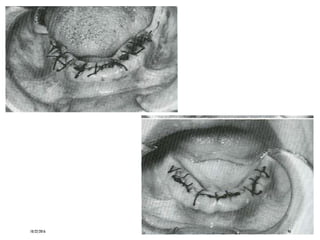

I, Tissue is closed with interrupted black silk sutures across papilla. This

vestibular height. J, Patient returns for suture removal 1 week later. Normal